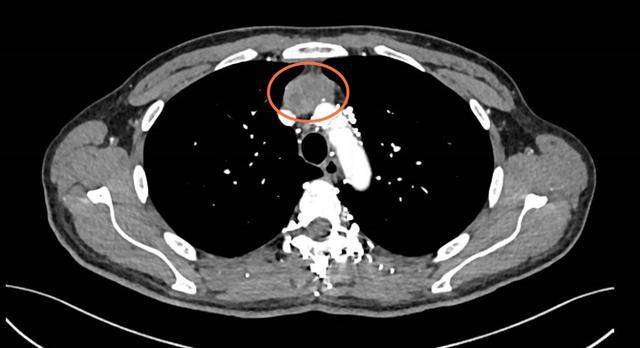

“一开始就是觉得胸口闷,后来连馒头都咽着费劲,走两步就喘得不行。”回忆起就诊前的日子,靳先生仍心有余悸。在河南省人民医院胸外科,检查结果让所有人都捏了把汗。CT(计算机层析成像)影像里,一个差不多拳头大小的纵隔肿瘤盘踞在胸腔里。更凶险的是,这颗肿瘤不仅死死裹住了上腔静脉(血液流回心脏的“主干道”),还咬破血管壁,钻进了心脏内部。

“血管已经被压得变了形,再晚一步可能完全堵死,到时候头脸肿、憋气会更严重,甚至肿瘤碎块掉下来,还会引发致命的肺栓塞。”胸外科主任魏立解释道。